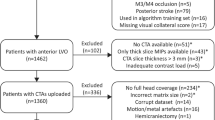

The MR CLEAN database contains data from 500 patients with acute ischemic stroke caused by an occlusion in the anterior circulation. Pre-interventional CTA scans were rated for CS and occlusion location by a core lab of radiologists without access to other imaging data or any clinical information. CTA scans with good/moderate image quality; adequate head coverage; axial series; slice thickness <1.0 millimetres; and slice increment equal to or smaller than slice thickness were selected. From those CTA scans, ten scans were randomly selected for each CS. Axial and coronal maximum intensity projections (MIPs) with slice thickness of 8 millimetres were reconstructed.

Selection of dataset and reference

From the 500 patients, 148 patients met inclusion criteria. For CS 0–3 (Fig. 1), based on image core lab evaluation, 10 CTA scans were randomly selected per collateral score. One scan could not be processed to create MIPs, which resulted in a test set with 39 cases. Figure 2 shows a schematic visualization of the patient selection. For the 39 selected cases, a reference CS was obtained after rereading the scans: CS 0 (n=5), CS 1 (n=13), CS 2 (n = 10), and CS 3 (n = 11) (Table 1). In 31% of the cases (12/39), a third radiologist was needed to provide consensus. CTA scan details (reference collateral score, slice thickness, peak kilovoltage (kVp), exposure (mA)) were reported (supplementary Table 1).